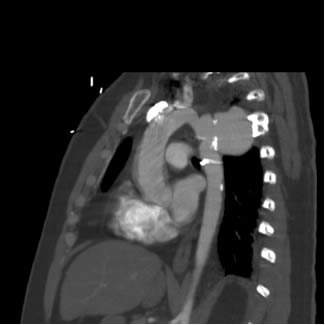

Diagnostic imaging of traumatic pseudoaneurysm of the thoracic aorta Serif Beslic, Nermina Beslic, Selma Beslic, Amela Sofic, Muris Ibralic, FIGURE 2A, B. CT of posttraumatic pseudoaneurysm of the aortic isthmus. presence of the posttraumatic pseudoaneurysm of the thoracic aorta. ... Read Full Source